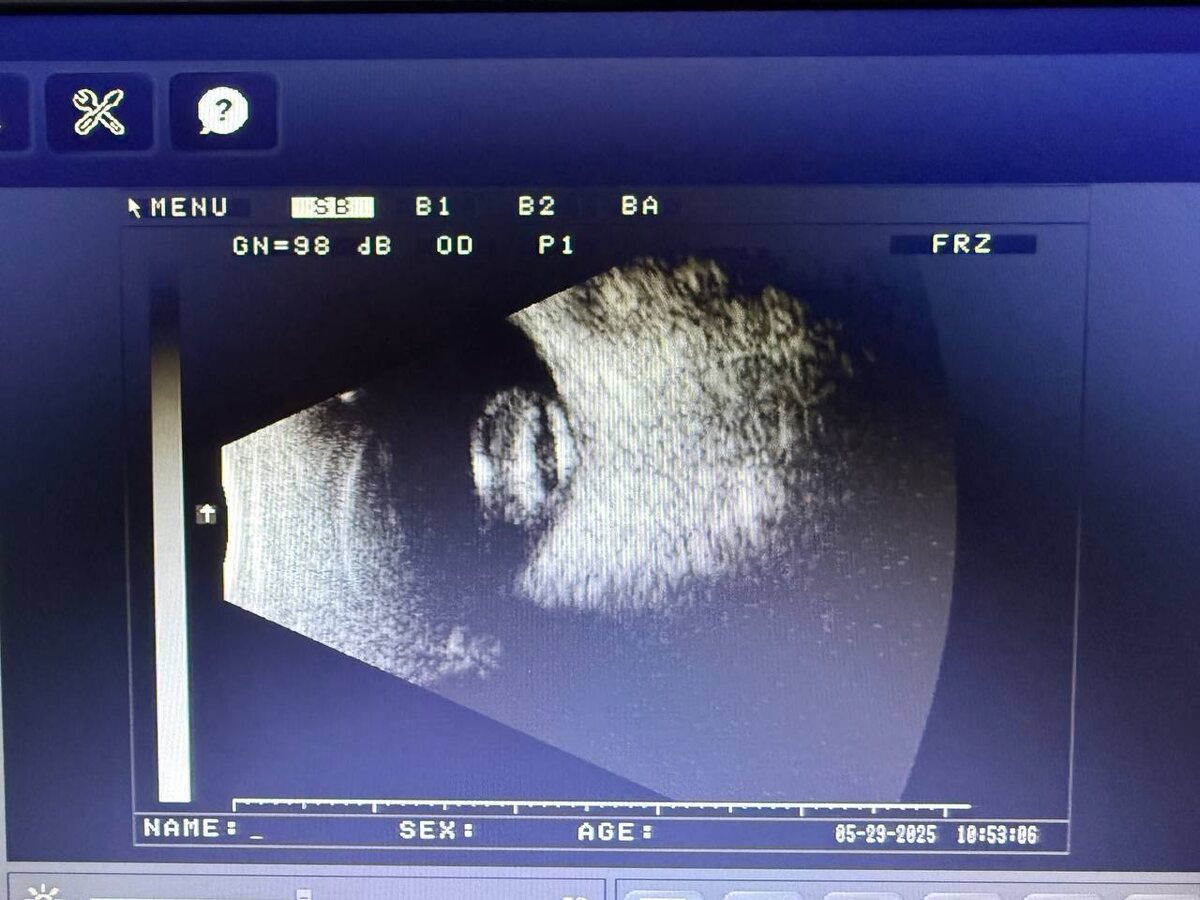

У пациентки 80+ глаз долгое время не видит, сперва была обычная катаракта, но в силу нежелания ее лечить, в конце концов, помутневший хрусталик решил утопится и сместился в витреальную полость. В положении лежа лежит на зрительном нерве, хорошо видно по УЗИ.

Ну а глаз ослеп не из-за этого, а из-за вторичной глаукомы, развившейся в конечном итоге.